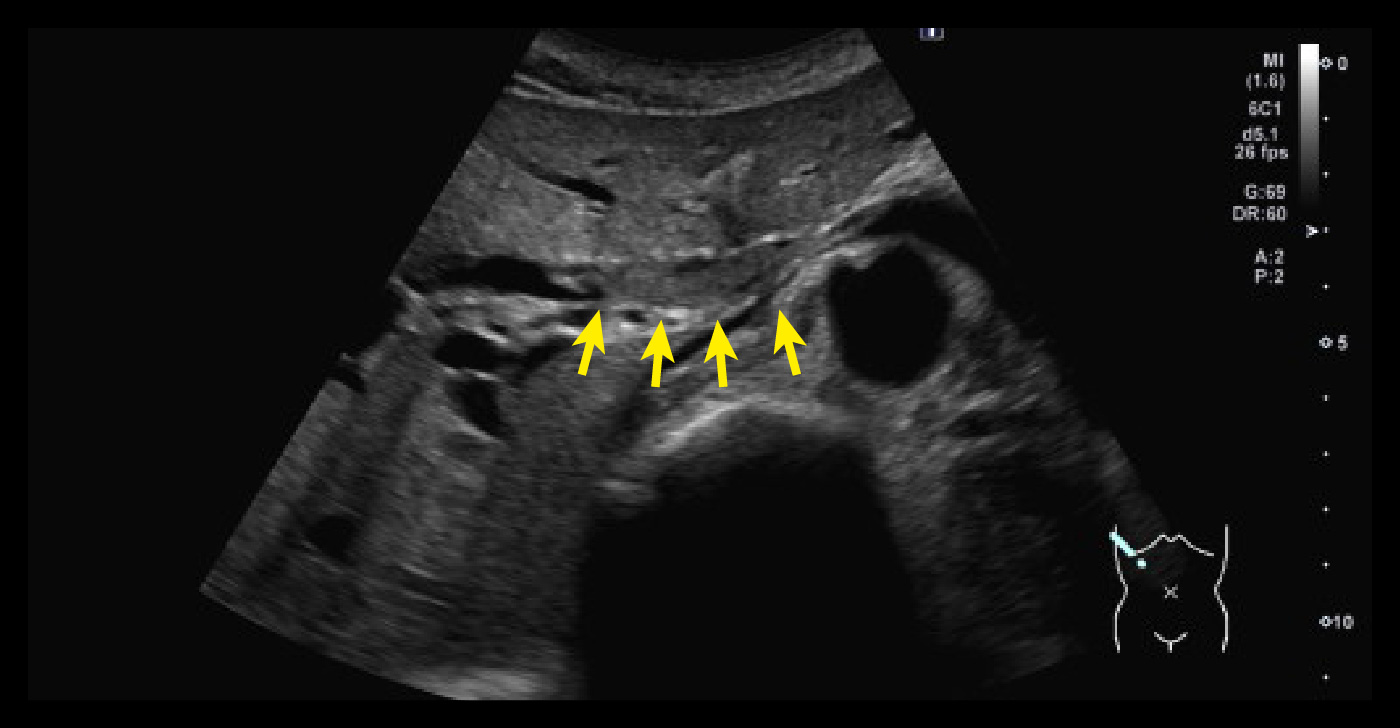

胆のう頸部内不整エコー像/右横隔膜方向 S8ac~S7へ膨隆腫大した胆嚢底部・体部

左から 胆のう頸部内不整エコー像/右横隔膜方向 S8ac~S7へ膨隆腫大した胆嚢底部・体部